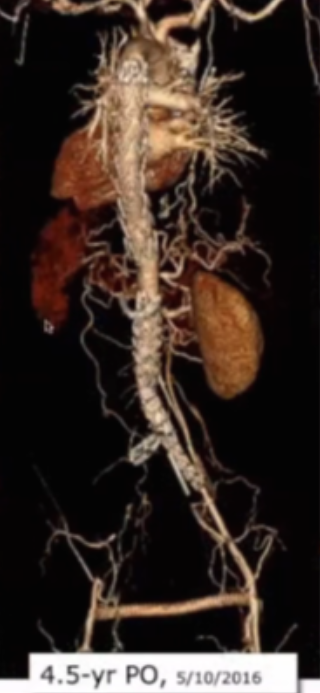

案例1:74岁男性患者,术前及6年瘤体的影像对比显示,动脉瘤瘤囊实现完全消退,体现出腔内治疗后长期的积极效果。

Complete aneurysm sac regression